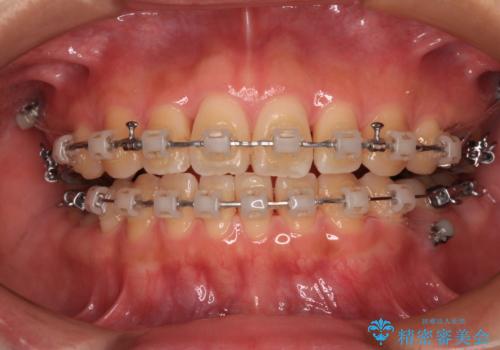

- 矯正装置

- クリアブラケット

- 下顎小臼歯が欠損しており、さらに上顎が全体的に突出していることを気にして来院された患者様です。

下顎は片方の小臼歯が欠損していたため、正中がずれた上に、上下前歯が接触していない状態でした。

上顎左右の小臼歯2本および下顎小臼歯を1本抜歯し、補助装置を用いて上顎大臼歯が前方に移動しないように固定した上で、ワイヤー装置にて矯正治療を行うこととしました。

上下前歯のズレは舌の突出癖による影響も大きいと考えられたたため、舌のトレーニングをしっかりと行っていただきました。